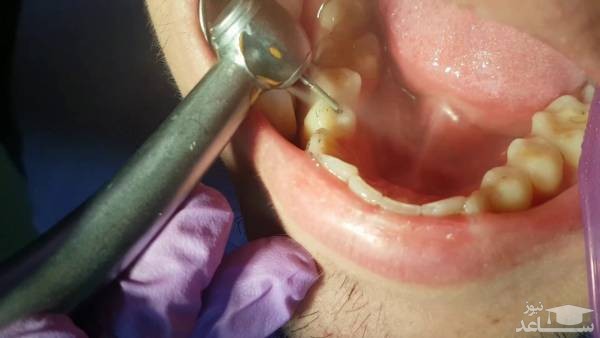

ابتدا دندان پزشک نواحی اطراف دندان پوسیده را بی حس می کند. سپس از یک وسیله برشی مانند مته و یا لیزر برای برداشتن قسمت پوسیده شده ی دندان استفاده می کند. انتخاب ابزار این کار بستگی به سطح راحتی دندانپزشک، آموزش، و سرمایه گذاری در قطعه خاصی از تجهیزات و نیز موقعیت و میزان پوسیدگی دارد.

در مرحله بعد دندان پزشک محل خالی شده از پوسیدگی را برای اطمینان از حذف کل پوسیدگی بررسی می کند. سپس به منظور آماده سازی دندان برای مرحله پر کردن، این حفره از باکتری ها و باقی مانده های پوسیدگی پاک می شود. در صورتی که این پوسیدگی نزدیک ریشه دندان باشد، ممکن است دندان پزشکتان از گلس اینومر، رزین کامپوزیت یا مواد دیگر برای محافظت از عصب استفاده کند. پس از پرکردن این حفره تقریبا کار دندانپزشک به پایان رسیده است و به صیقل آن دندان می پردازد.

انجام چند مرحله ی اضافی دیگر برای پر کردگی های رنگِ دندان لازم است. پس از آنکه دندان پزشک پوسیدگی را برداشت و محل را پاکسازی کرد، حفره با مواد رنگِ دندان به صورت لایه لایه پر می شود. سپس با تاباندن اشعه خاصی، هر لایه محکم می شود. پس از اتمام این مرحله، دندانپزشک مواد رزین کامپوزیتی که دندان را پر کرده است را شکل می دهد و قسمت های اضافی را حذف می کند و درآخر آن را صیقل می دهد.